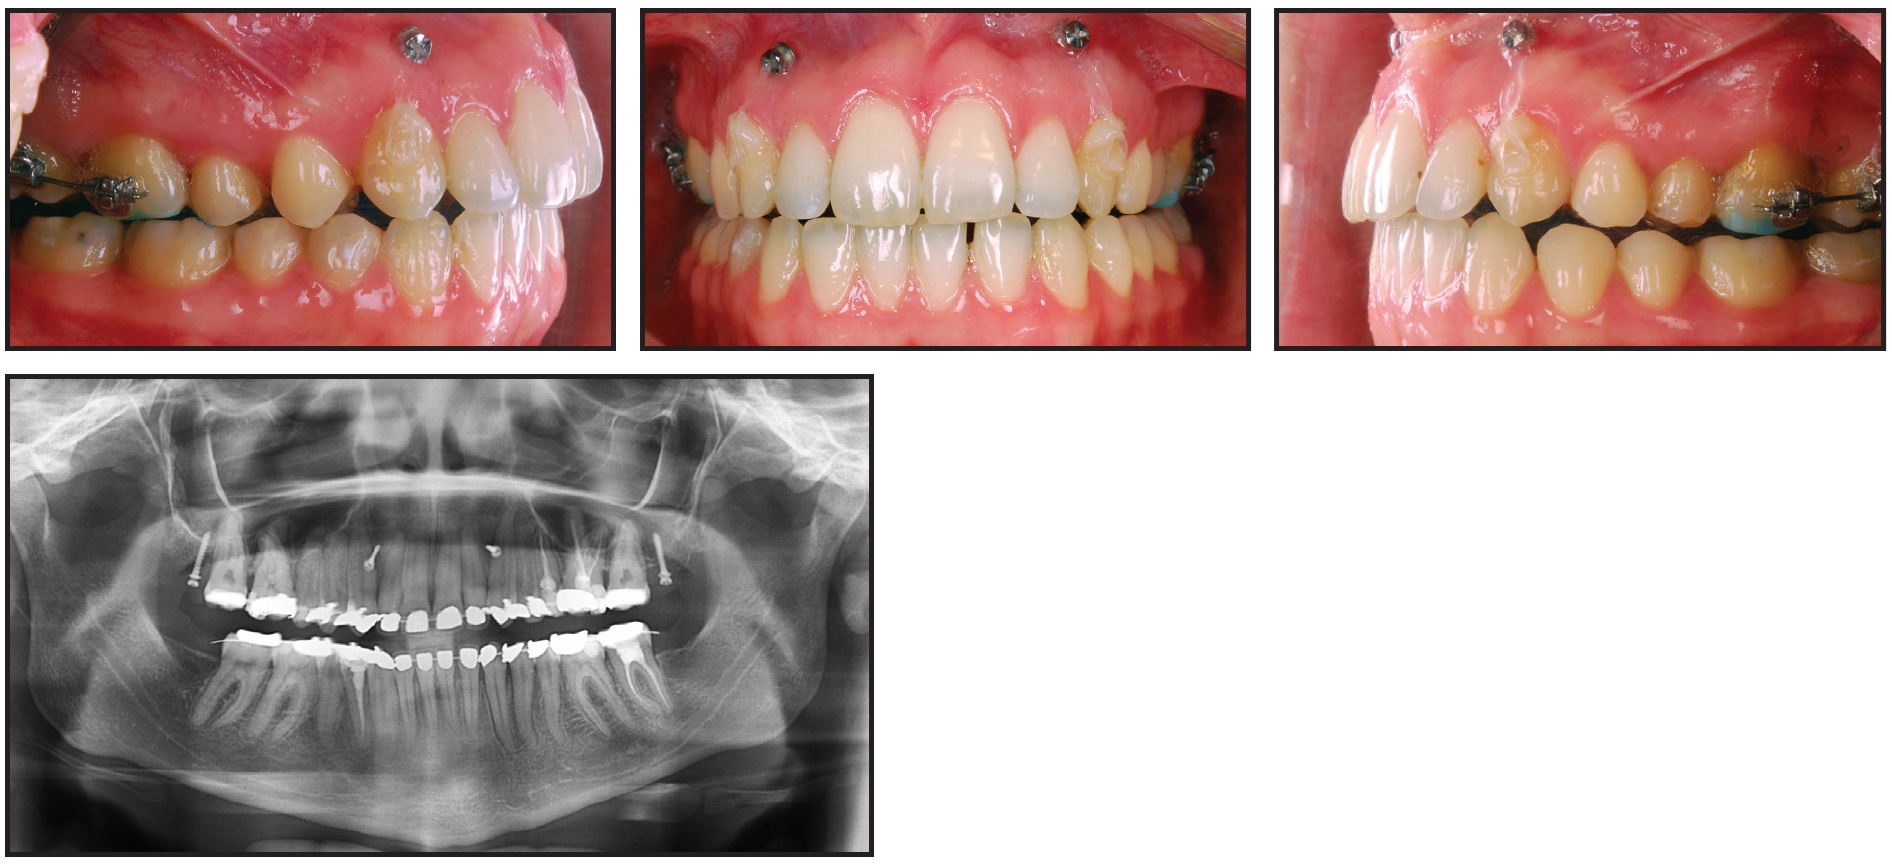

A 25-year-old female patient presented with a skeletal Class II pattern, Class II molar and canine relationships (complete on the left and edge-to-edge on the right), excessive overjet, and a narrow maxilla (Fig. 1).

Fig. 1 25-year-old female patient with skeletal Class II pattern, excessive overjet, and anterior open bite before treatment.

Her mouth-breathing habit had caused gingivitis of the upper incisors, and her vertical mandibular plane had led to lip incompetence that made it difficult to close her lips at rest. She displayed an open bite from premolar to premolar, a crossbite on the left side, and moderate crowding of the upper and lower anterior teeth. The upper and lower occlusal planes were tilted from left to right, causing the mandible to show a slight deviation to the left. The upper third molars were present, but the lower right had been extracted and the lower left was mesially impacted.